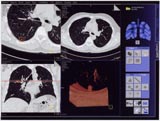

「Lung CARE」の主な特長

1〜3mm厚の胸部画像を操作画面上でアニメーション表示することによって,8〜10mm厚の画像を1枚ずつ読影していたこれまでと比べ,より精密かつ読影効率が向上。

〈微小な病変部位の検診をサポート〉

疑わしい箇所を回転MPR像にして,結節と正常な血管との違いといった,微小な病変部位の検診をサポートする。